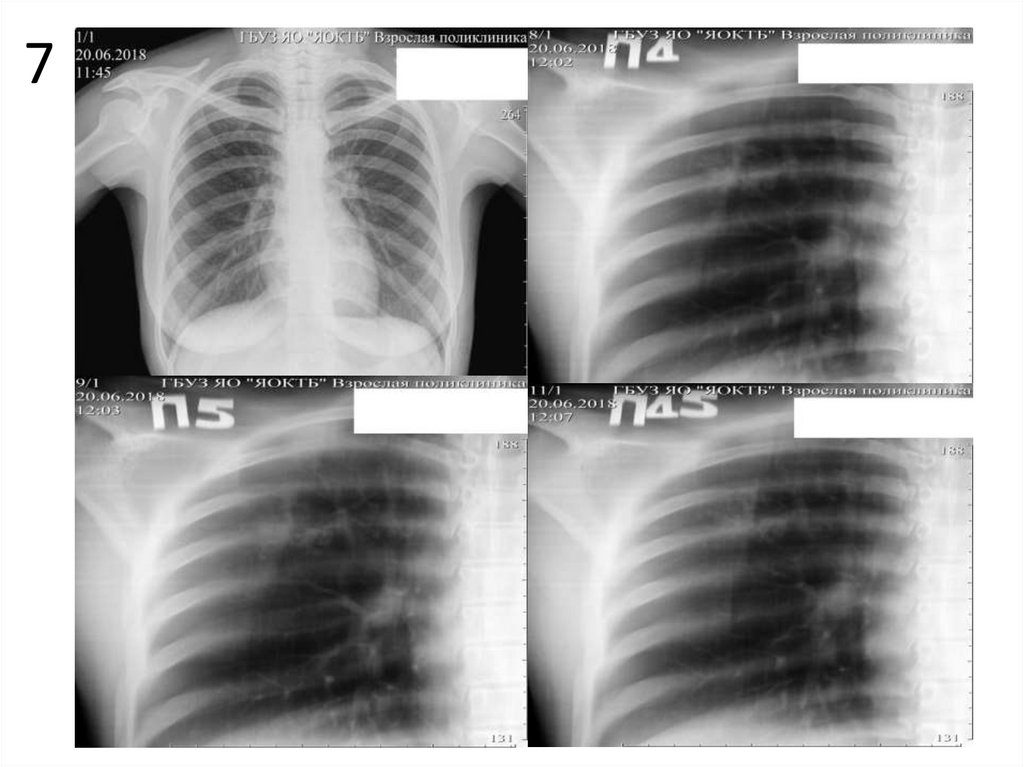

7